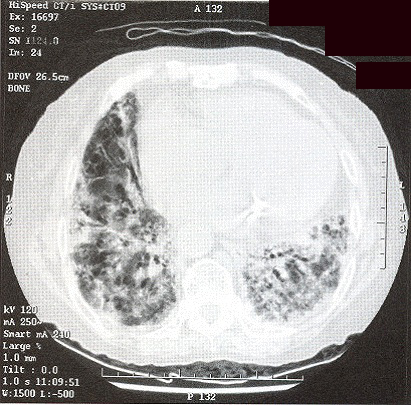

Initially, she was treated as community acquired pneumonia. However her symptom did not improve and she got persistent low-grade fever. CXR showed even more extensive shadow. Bronchoscopy was performed but no endobronchial lesion was found. Transbronchial biopsy was taken from left lingular lobe showed non-specific inflammation. Neither malignant cell nor acid-fast bacilli was found. CT thorax (Fig 3 & 4) was performed which showed widespread ill-defined patchy and nodular opacities and small reactive mediastinal lymph node. CT guided fine-needle aspiration of lung opacity was perfonned but material obtained was insufficient for diagnosis. Her general condition deteriorated despite multiple course of antibiotics treatment. She developed type 1 respiratory failure with oxygen dependency. Open lung biopsy was arranged but was withheld due to poor respiratory reserve. Another session of bronchoscopy was performed. This time the transbronchial biopsy showed evidence of diffuse alveolar damage. Her condition deteriorated further and became bed-ridden. On further questioning, amiodarone has been taken by patient for cardiac problem for few years and was stopped few months prior this admission due to bradycardia. Amiodarone pulmonary toxicity was suspected and oral prednisolone with a dose of Img/kg/day was started.

Figure 6